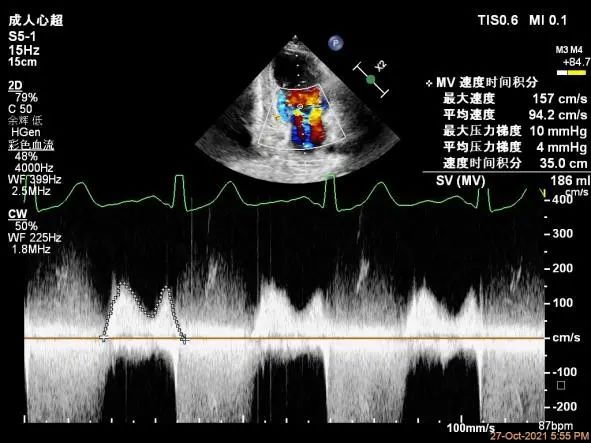

二尖瓣口平均跨瓣压差:4mmHg

夹子放置后二尖瓣口平均跨瓣压差:1mmHg

肺静脉血流频谱恢复正向